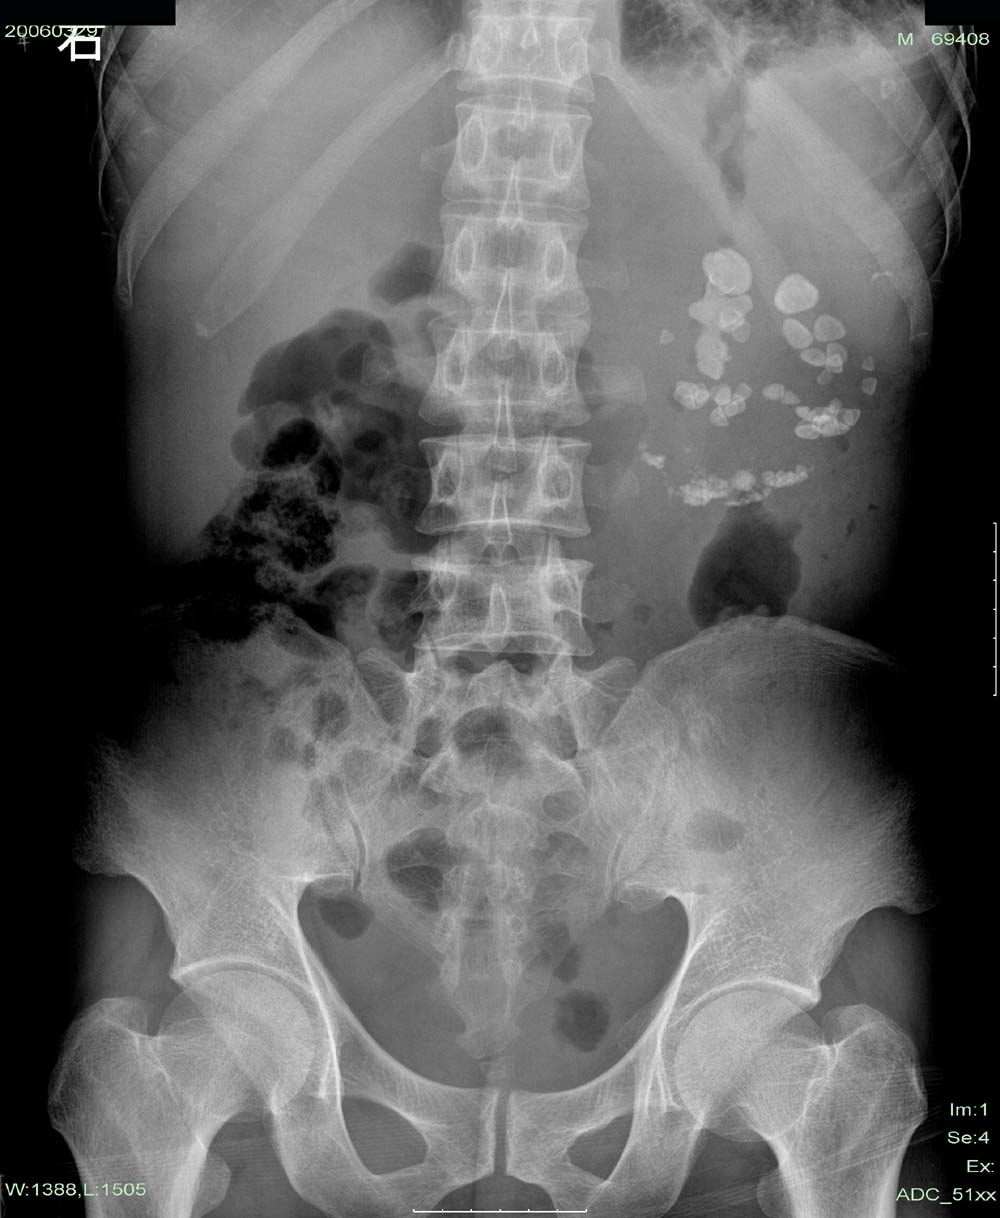

患者,青年男性,左侧腰疼1年余。年前出现尿频、尿急症状。

b超认为左肾多发性结石伴重度积水。

可是我个人认为是:左侧自截肾伴左肾排泄功能丧失。

这个是左肾多发性结石伴重度积水。其与肾自截不同的是:肾自截呈全肾钙化,肾脏缩小.本例肾内密度增高影呈颗粒状,肾影增大.故不支持肾自截

本例造影过程中结石位置,大小等都未有明显改变。左肾体积明显增大,与肾自截相反。且无钙化。故支持向医生的观点。

左肾上极见“鹿角”样结石并中下极多发性结石。左肾重度积水,在该片只是推理而已,左肾没有看到肾盂、肾盏显影。从结石分布看,可以肯定不是肾自截钙化。